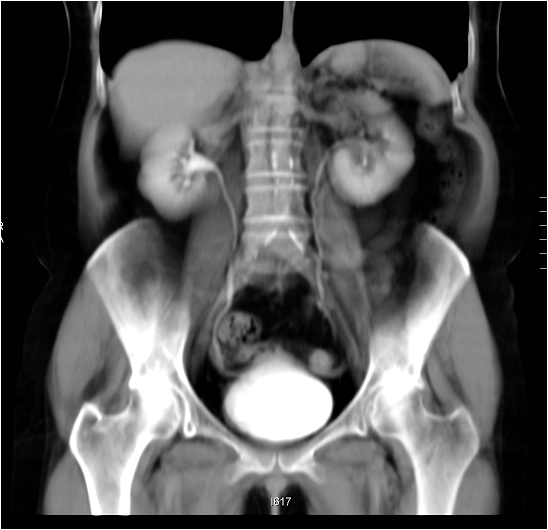

TCCs in 80% of the cases have a polypoid appearance. The lesion causes filling defect on the intravenous pyelogram and on the excretory phase CT scans, when contrast media is being secreted to the renal pelvis.

Image

Figure 6. CT image of an extensive right pelvic tumor on excretory phase coronal CT scans.